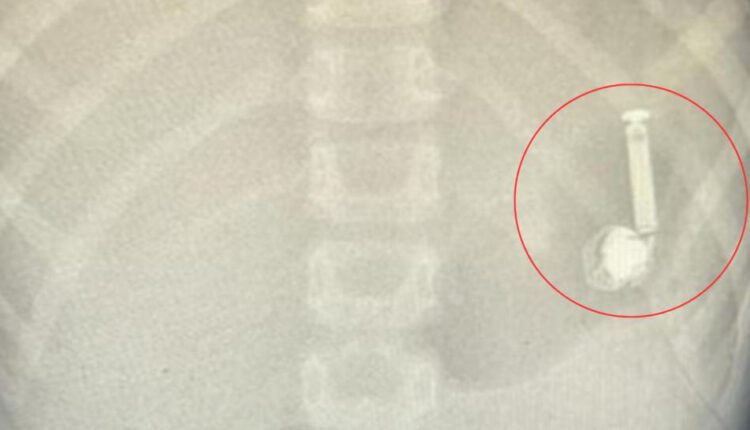

وصلت الحالة لقسم الطوارئ بالمستشفى، وأخبر الأهل الطاقم الطبي بأن ابنهم ابتلع السماعة، وعلى الفور تمت مناظرة الحالة وعمل الفحوصات الطبية اللازمة، وشُكّل فريق طبي من قسم المناظير والتخدير؛ للتعامل مع الحالة وتجهيز الطفل لعمل المنظار دون تدخُّل جراحي.

وتكللت العملية بالنجاح في وقت قياسي تم على إثره إزالة السماعة، والتأكد من صحة الطفل، وغادر المستشفى وهو يتمتع بصحة جيدة.